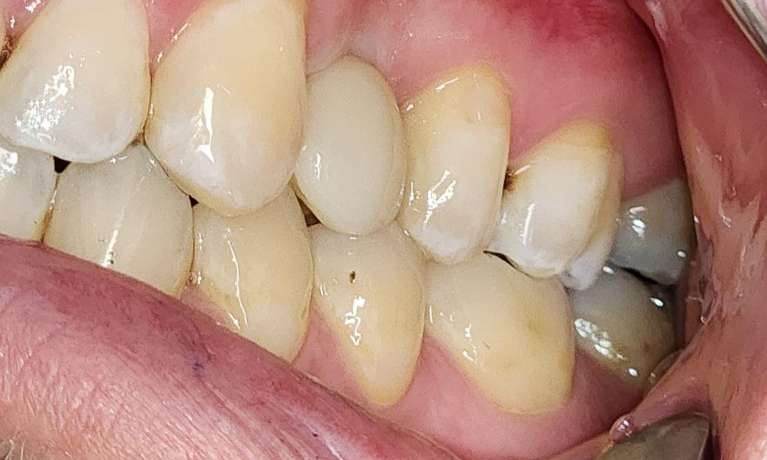

For this patient, dental implants were used to replace missing back teeth to help reestablish chewing efficiency and improve overall oral function.